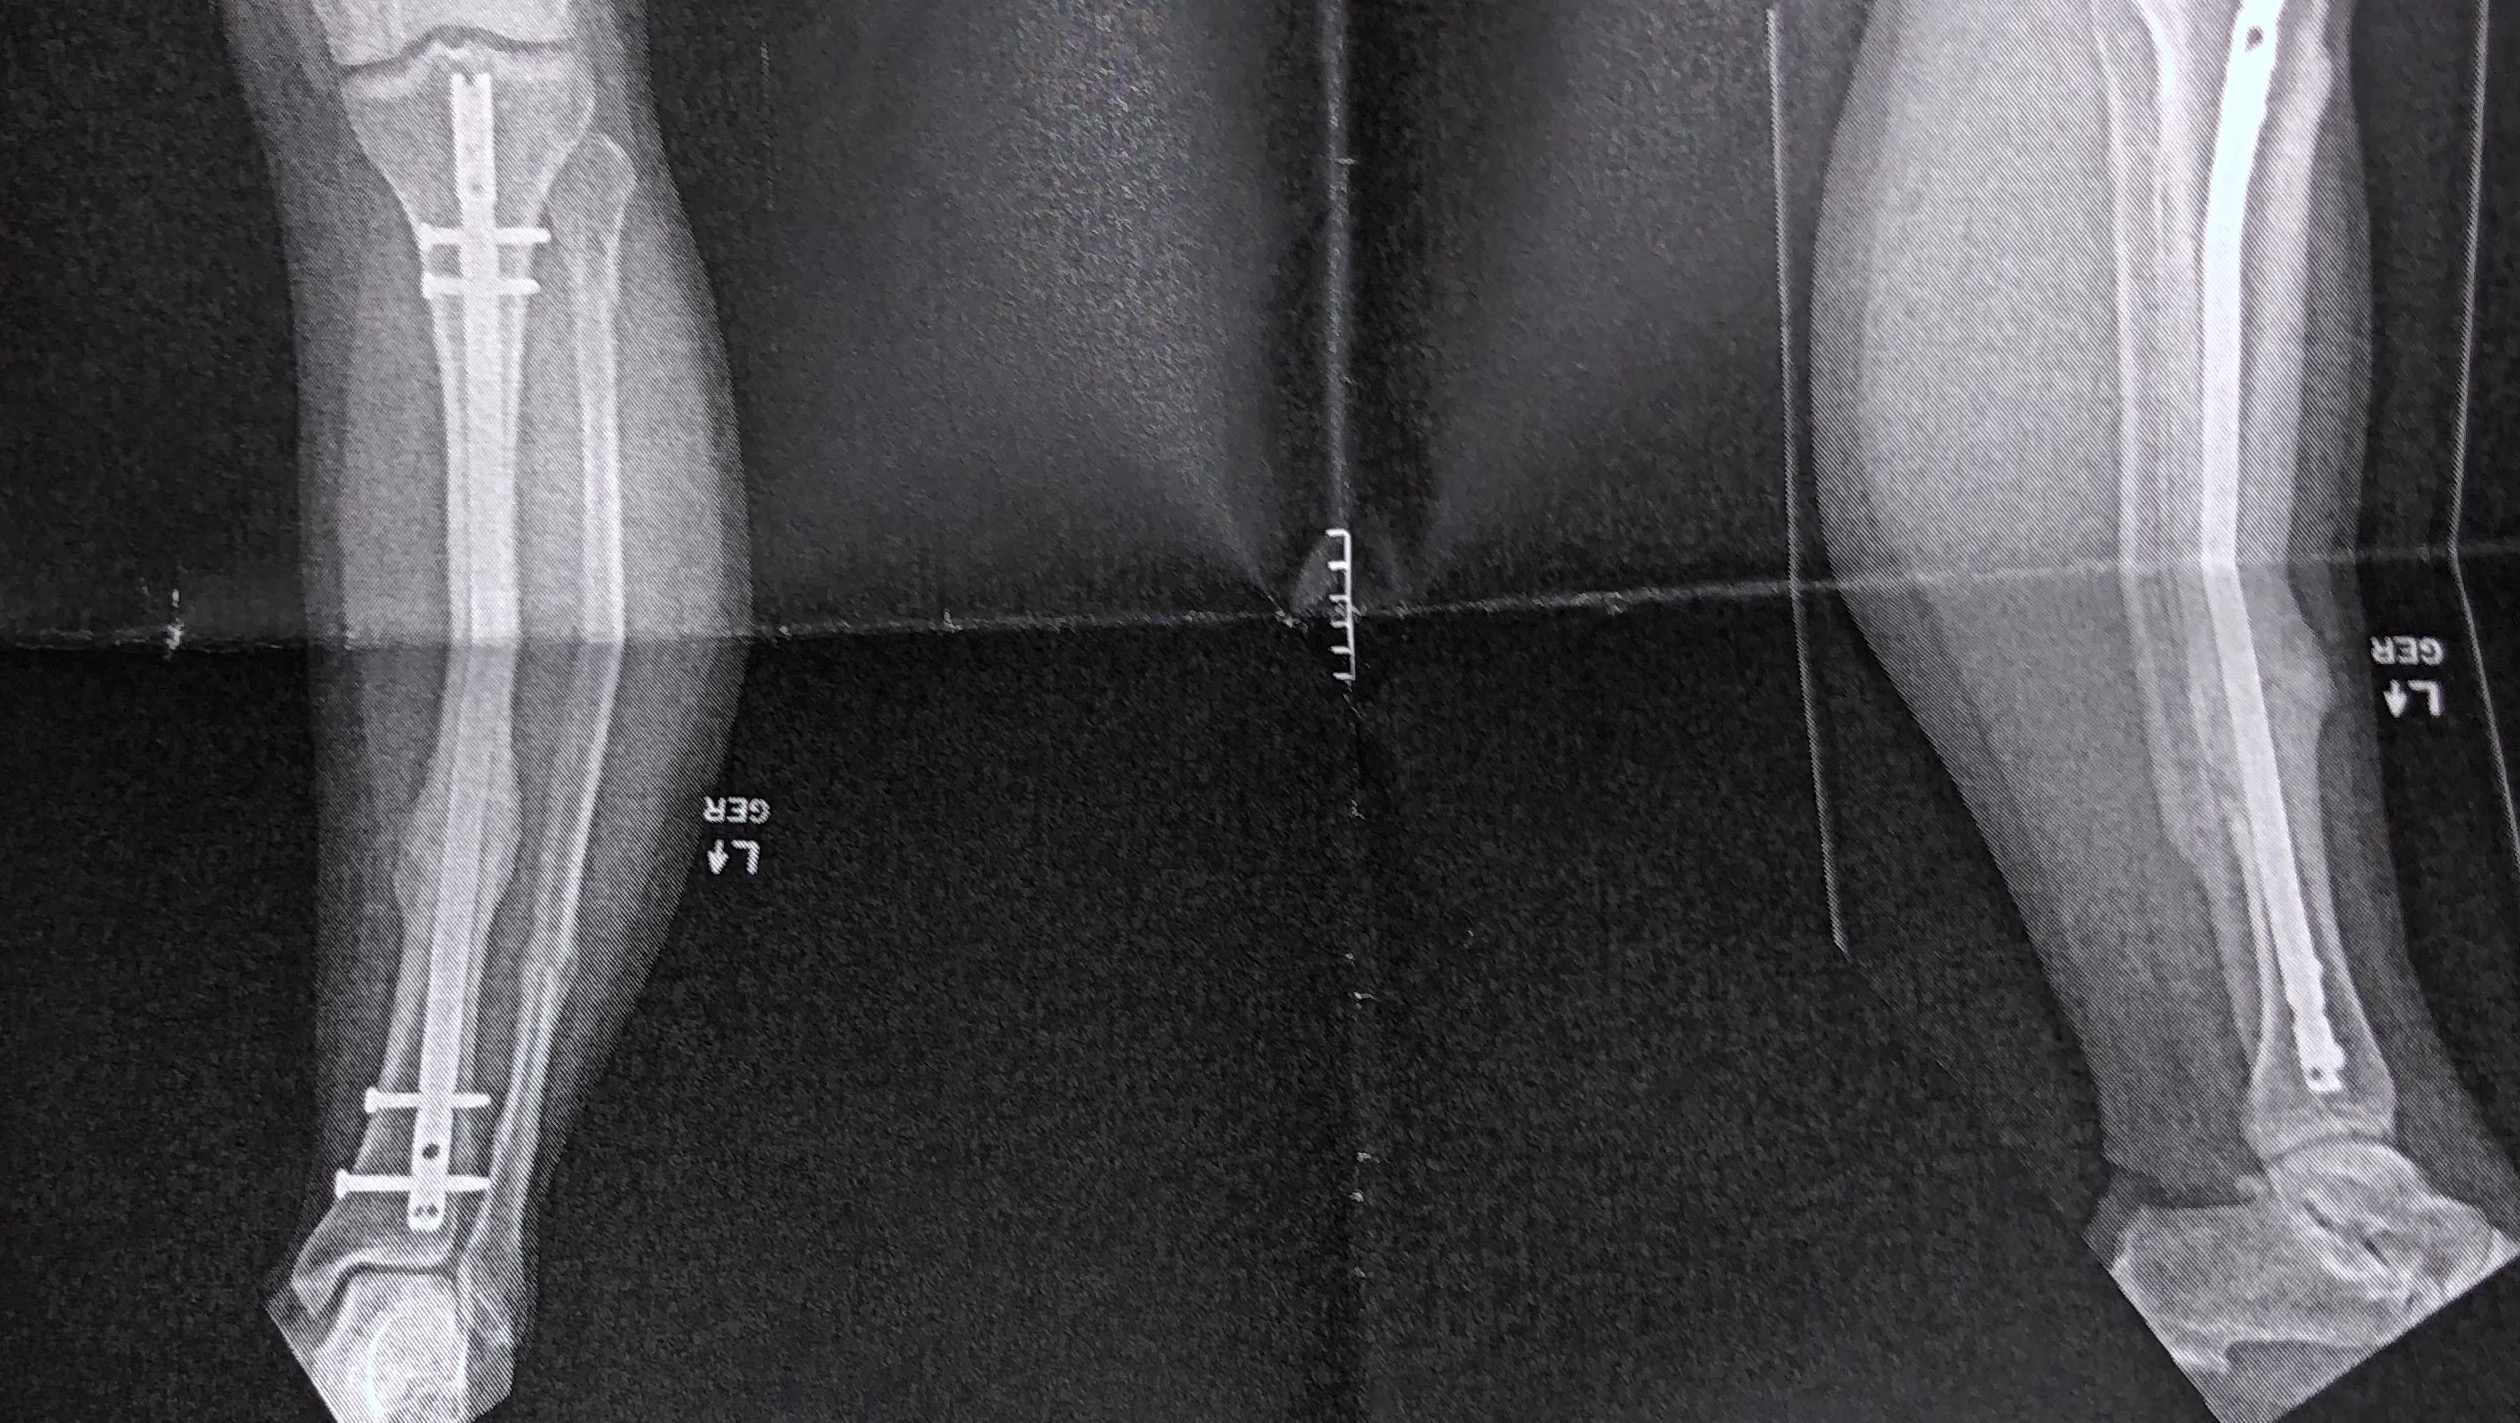

Please, anyone, I need help. We are about to lose our home!!! We don’t want to lose our home, our pets, our dogs, our cats, or everything inside our home. I had a very bad, God-awful wreck at the end of 2020 that left me unable to do just about anything, let alone be able to work to provide for my family. My wife had to take on the role of working, but it is not enough for the mortgage and utilities, and we’ve gone through all of our funds to stay above water.